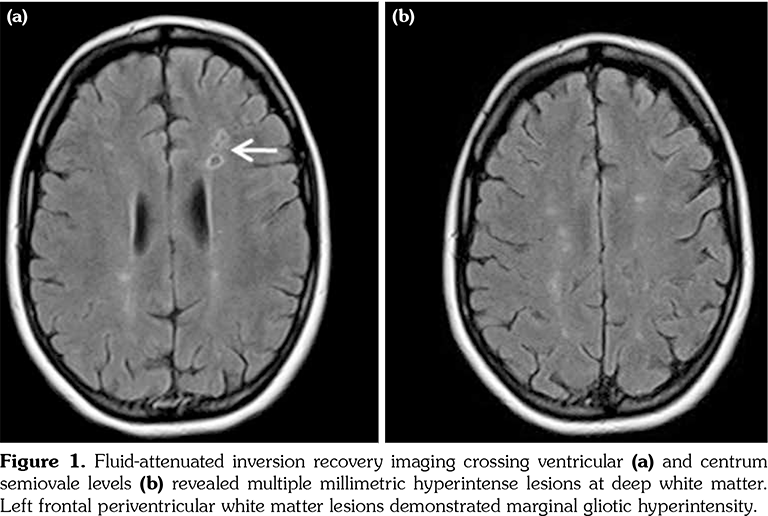

A 14-year-old female patient referred to our clinic with headache and dizziness for two weeks and loss of consciousness for about 10 minutes. On admission, the blood pressure was 90/60 mmHg and all peripheral pulses were palpable. Her body weight was above 97th percentile for her age and body mass index was 33. The fundus examination and other organ systems were essentially normal. Laboratory studies revealed erythrocyte sedimentation rate (ESR) as 108 mm/hour and C-reactive protein (CRP) as 7.5 mg/dL (0-0.8), while other measurements were normal. Urinalysis revealed microscopic hematuria and proteinuria of 31.9 mg/m2/hour in 24-hour urine collection. The cerebrospinal fluid examination showed no abnormalities. Cranial magnetic resonance imaging (MRI) showed multiple millimetric hyperintense deep white matter lesions on T2-weighted imaging (Figure 1). Intracranial and extracranial arteries were normal in magnetic resonance angiography (MRA). Renal biopsy findings were interpreted as FSGS (Figure 2). Patient was considered as cerebral vasculitis and incidental FSGS. Pulse methylprednisolone therapy for three consecutive days was initiated and continued with oral prednisolone. At four years of follow-up, proteinuria decreased to 5-15 mg/m2/hour, and ESR and CRP were normal. Repeated brain MRI and MRA examinations showed no new lesions. Four years later, at the age of 18, on a routine examination, both radial artery pulses were absent and the blood pressure could not be measured. Significant bruit was heard on the left carotid artery. Laboratory studies revealed ESR as 43 mm/hour and CRP as 2.46 mg/dL. Aortic MRA revealed diffuse wall thickening and contrast enhancement in the arcus aorta and its many main branches (Figure 3). Takayasu arteritis diagnosis was established according to the European League Against Rheumatism/ Paediatric Rheumatology International Trials Organisation/Paediatric Rheumatology European Society criteria.[2] Methotrexate was begun, and daily prednisolone was continued. Four months after the diagnosis of TA, left-sided hemiparesis developed. Brain MRI demonstrated a wide cerebral infarct at the right anterior vascular territory (Figure 4). Brain and neck computed tomography angiography showed total occlusion of the right internal carotid artery. Vascular involvement of the right common carotid artery was progressed to preocclusive stenosis. Diameters of the right anterior and middle cerebral arteries were thin and fed by the posterior and anterior communicating arteries (Figure 5). Tocilizumab treatment was started at 8 mg/kg every four weeks. At follow- up with 2.5 years of tocilizumab treatment, the patient's clinical condition improved slightly, and no new symptoms developed. A written informed consent was obtained from the patient.